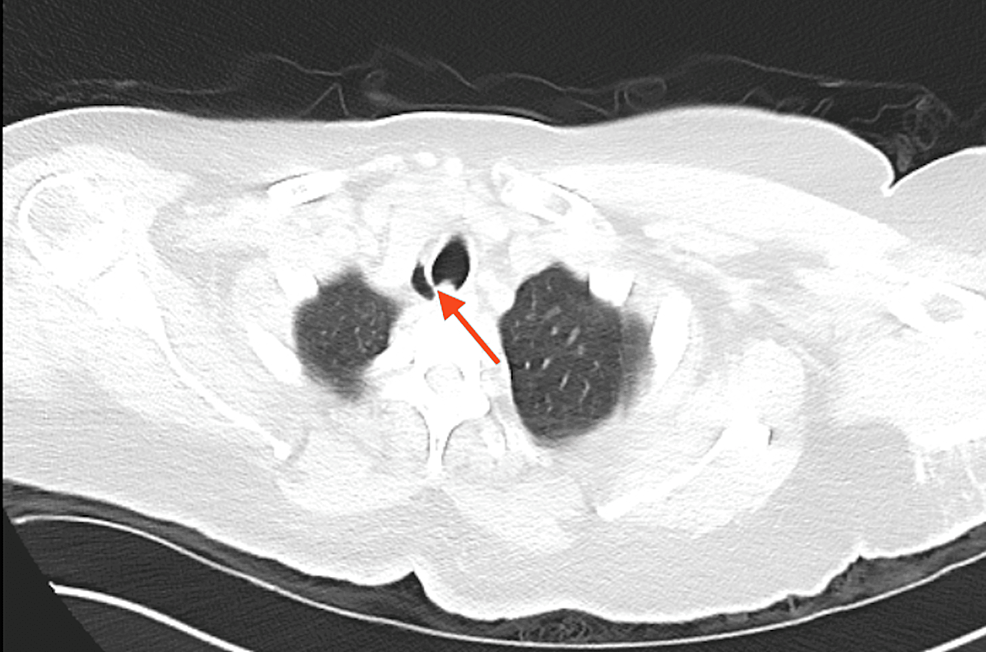

Tracheal diverticulum Image Tracheal Diverticulum Anesthesia Tracheal diverticulum is a rare and often incidental diagnosis found on chest imaging in an asymptomatic patient with. Tracheal diverticula are rare congenital or acquired abnormalities of the posterior tracheal wall. Tracheal extubation requires a clear strategy to avoid complications and keep patients safe. Tracheal diverticula are extremely rare. This strategy should include risk assessment, planning and preparation. Tracheal diverticulum. Tracheal Diverticulum Anesthesia.

From radiopaedia.org

Tracheal diverticulum Image Tracheal Diverticulum Anesthesia Tracheal diverticula are rare congenital or acquired abnormalities of the posterior tracheal wall. Tracheal diverticula are extremely rare. Tracheal diverticulum is a rare and often incidental diagnosis found on chest imaging in an asymptomatic patient with. Tracheal extubation requires a clear strategy to avoid complications and keep patients safe. Tracheal diverticulum (dv) is a type of paratracheal air cyst (ptac). Tracheal Diverticulum Anesthesia.